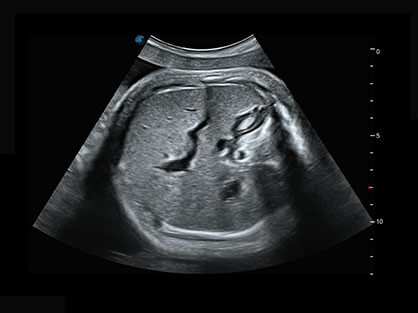

作为P系列家族成员之一,P40 Plus采用银河集团官网高端超声系统平台——极光,并以时尚秀丽、小巧灵动的外观设计绽放出灵动之韵、科技之美。高端平台的使用保证了P40 Plus优质的基础图像;完备的高级功能可满足您全身应用的基本需求;丰富的探头配置、多样的高级4D成像及分析软件为您日益增多的妇产应用需求提供丰富的诊疗方案。

结合银河集团官网超宽频带探头技术优势,能够更好地获得高分辨力与高穿透力的平衡,保证图像质量,为临床诊断保驾护航。

宽频带腹部凸阵探头和腹部容积探头、大角度腔内探头和腔内容积探头、独特的生殖专用曲柄探头,为妇产应用提供全面诊疗方案。